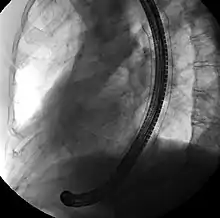

A self-expandable metallic stent (or SEMS) is a metallic tube, or stent that holds open a structure in the gastrointestinal tract to allow the passage of food, chyme, stool, or other secretions related to digestion. Surgeons insert SEMS by endoscopy, inserting a fibre optic camera—either through the mouth or colon—to reach an area of narrowing. As such, it is termed an endoprosthesis. SEMS can also be inserted using fluoroscopy where the surgeon uses an X-ray image to guide insertion, or as an adjunct to endoscopy.

Esophageal SEMS are placed after a gastroscopy is performed to identify the area of narrowing. The area may need to be dilated to allow the gastroscope to pass.[14] The tumour is usually better seen with the direct vision of endoscopy than on a fluoroscopic image. As a result, radio-opaque markers are usually placed on the surface of the patient to mark the area of narrowing on fluoroscopy. The SEMS is placed through the channel of the endoscope into the esophagus over a guidewire, marked on fluoroscopy, and mechanically deployed (using a device that sits outside of the endoscope) such that it expands when in position. Hypaque or other water-soluble dye may be placed through the passage to ensure patency of the stent on fluoroscopy.[15] Enteric and colonic SEMS are inserted in a similar fashion, but in the duodenum and colon respectively.[16]